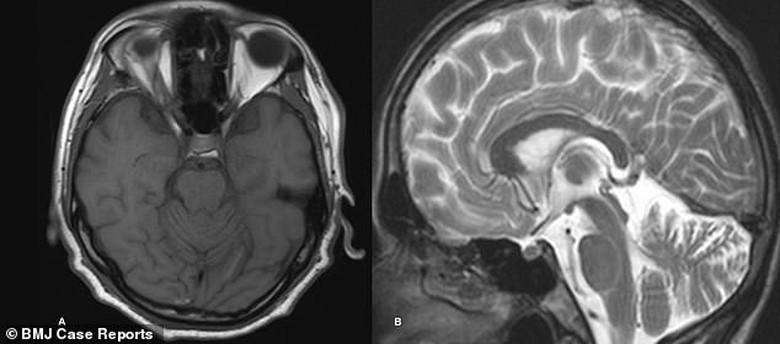

Mặc dù các xét nghiệm thông thường cho thấy người này vẫn trong tình trạng tương đối khỏe mạnh. Tuy nhiên, khi được chụp MRI não, các dây thần kinh khu vực tiểu não đang chết dần.

Các bác sĩ đã không còn nghi ngờ gì nữa rằng, điều này có liên quan đến kết quả xét nghiệm dương tính với Treponema pallidum, vi khuẩn gây bệnh giang mai.